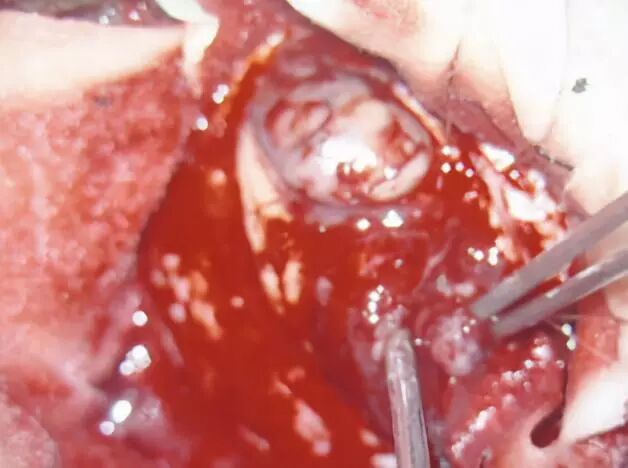

右侧小脑半球见团片状不均匀长T1长T2信号影,DWI局部高信号,增强扫描可见不均匀环形强化,病灶边界欠清,范围约为48mmX19mm,周围可见水肿带(图1)。影像学诊断:首先考虑感染性病变伴脑脓肿形成,肿瘤不能排除。MRS检查示:NAA明显下降,Cho峰升高,Cho/NAA比值增高。Cr峰降低,宽大LL峰出现,诊断考虑病变坏死明显,梗塞局部软化或脓肿(如寄生虫感染)可能,不支持脑肿瘤诊断(图2)。

图2. MRS中ROI 19区提示:NAA明显下降,Cho峰升高,Cho/NAA比值增高。Cr峰降低,宽大LL峰出现,诊断考虑病变坏死明显,梗塞局部软化或脓肿(如寄生虫感染)可能。

在1H-MRS上高胆碱(Cho)峰、低N-乙酰天冬氨酸(NAA)峰与肿瘤侵袭性密切相关。研究表明髓母细胞瘤在MRS会表现为Cho峰、Cho/肌酸(Cr)比值及Cho/NAA比值显著升高,NAA峰明显降低,并且髓母细胞瘤Cho峰明显高于其他后颅窝肿瘤[6](图9)。同时在MRS中选择短TE(20ms)的激励回波成像,可检测到所有髓母细胞瘤均出现了牛磺酸(Tau)峰,其共振峰位于3.3ppm,认为Tau是髓母细胞瘤特异性的生物标记物[6]。